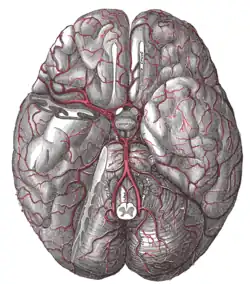

Sistema endócrino Artérias da base do cérebro

Artérias da base do cérebro Cérebro seccionado no plano sagital mediano

Vascularização

As artérias para a hipófise são as artérias hipofisárias superiores, ramos da carótida interna ou da artéria comunicante posterior, e as artérias hipofisárias inferiores, ramos da carótida interna mas atravessam o seio cavernoso. Os ramos das artérias superiores abastecem a haste e as partes adjacentes do lobo anterior. Os ramos das artérias inferiores suprem o lobo posterior. A suplência sanguínea da parte distal é feita sobretudo através de veias de um sistema porta. O sangue dos capilares da parte tuberal e adjacências da haste drena para as veias, que descem ai longo do infundíbulo e terminam em numerosos capilares sinusoídes da parte distal.

As veias da hipófise são as veias hipofisárias laterais que drenam para os seios cavernosos e intercavernosos.